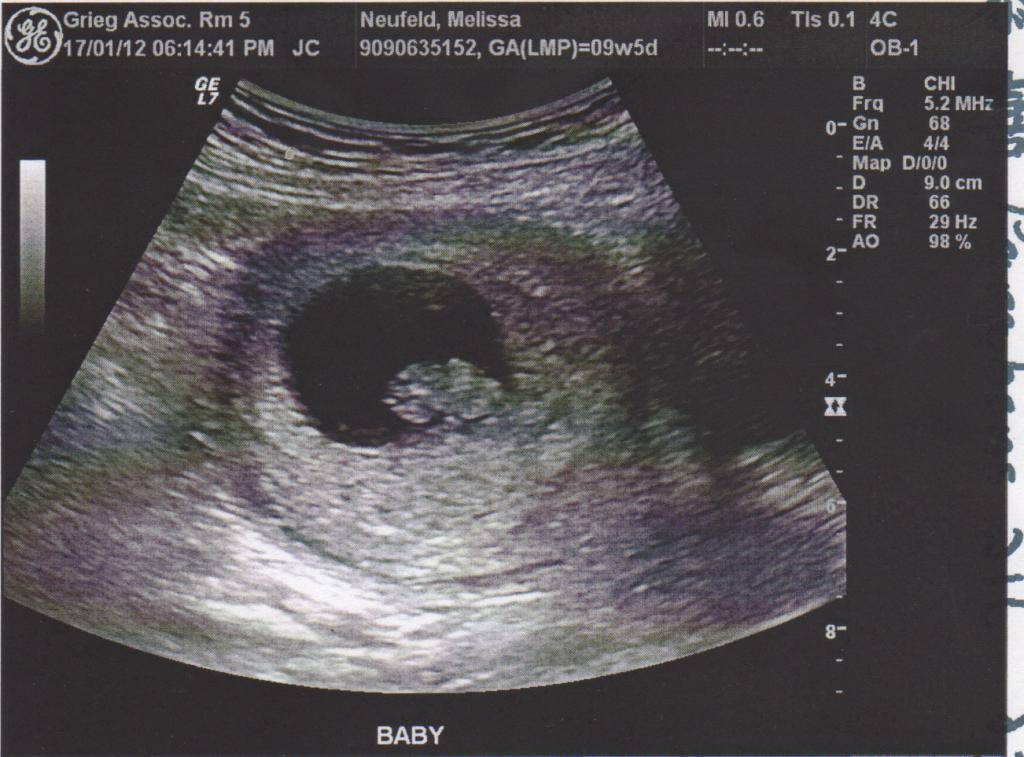

В ходе УЗИ плодное яйцо обнаруживается в виде маленькой черной точки. В нем хорошо видно расплывчатое белое пятнышко – эмбрион. Исследование проводят трансвагинальным способом. Плодное яйцо представляет собой анэхогенное (не отражающее ультразвуковые волны) образование округлой или овальной формы. Микроскопические размеры эмбриона в самом начале его развития не дают возможности увидеть его с помощью УЗИ. На ранних сроках сонолог выявляет беременность и определяет ее срок, обнаруживая плодное яйцо и измеряя его.

Плодное яйцо

Когда беременность, без сомнений, есть, доктор пишет, что в маточной полости визуализируется плодное яйцо. Внимательному исследованию подвергается его форма и размер. Главный параметр определяется по внутреннему среднему диаметру (этот размер в заключении указан, как СВД).

является бесспорным подтверждением факта беременности, но оно не может быть параметром, определяющим точный срок, ведь форма этого образования — особенность индивидуальная. В среднем размер плодного яйца на этой неделе варьируется от 24 до 30 мм.

СВД на 8 неделе беременности:

Средний диаметр плодного яйца внутри, мм | Акушерский срок |

19 (минимальное значение 8) | + 0 дней |

20 (минимальное значение 9) | 7 недель + 1 день |

21 (минимальное значение 10) | 7 недель + 2 дня |

22 (минимум 11) | 7 недель + 3 дня |

23 (минимум 12) | 7 недель + 4 дня |

24 (минимум 13) | 7 недель + 5 дней |

25 (минимум 14) | 7 недель + 6 дней |

На восьмой неделе все еще оценивают состояние желточного мешочка — особого органа — «пищевого склада» эмбриона, который существует только на самых , а потом исчезает. В норме диаметр этого мешка на составляет 4,0-4,5 мм. Начиная с 10 недели он уменьшается, и постепенно исчезает, передавая свои функции сформировавшейся .

Эмбрион

В норме доктор на 8 неделе определяет живой эмбрион внутри плодного яйца. О том, что кроха, размер которого всего около 4-5 мм, жив, может говорить его и первые движения. Если малыш подает признаки жизни, то доктор измеряет его от головы до копчика. И это пока единственная «мерка», которую можно снять, другие части тела и органы пока измерить невозможно.

КТР

Значительно больше о сроке и развитии крохи-эмбриона может рассказать этот размер. За аббревиатурой кроется «копчико-теменной размер», то есть расстояние от копчика до макушки. Если к заключению приложен снимок, то этот отрезок на первом «фото» малыша обозначен отрезком.